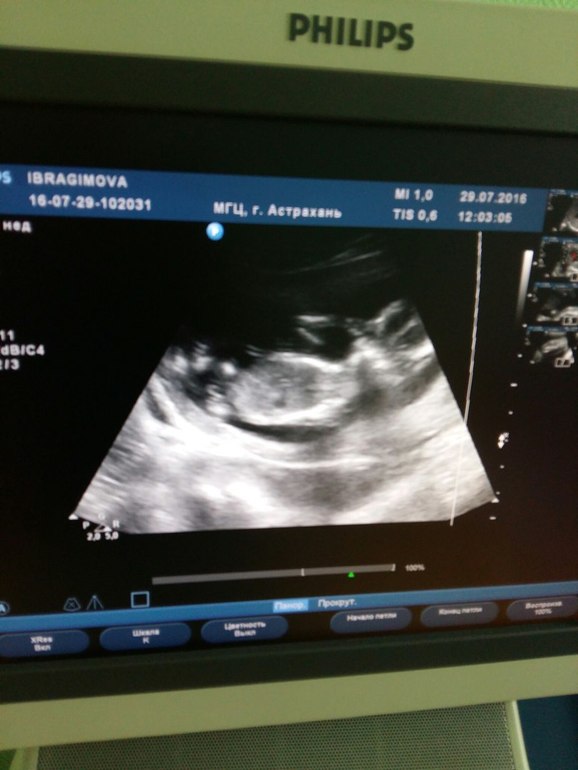

Решила начать ведение дневника с 1-го скрининга малыша.

Приехала заранее и очень долго ждала... наконец меня приняли и... все было так быстро и сухо... что я не сумела понять что вообще происходит... Сначала врач с каменным лицом вглядывалась в экран и долго молчала, потом начала говорить медсестре какие-то медицинские термины для записи в карточке. Когда она заговорила и включила сердцебиение я успокоилась... мой малыш на месте... единственное я представляла себе это по другому... в конце концов я не выдержала и спросила все ли в порядке и все ли на месте, она ответила что да, можно одеваться и сделать снимок с экрана. и все... это все...

Я взяла карточку и вышла в коридор... ну и сделала фотку экрана...

Вот такой вот у меня интересный малыш...) мне показался очень даже милым...)

а еще прилагаю результаты скрининга... у нас определают только количество рук ног, а пальчики не считают, и длину кости носовой тоже не определяли... Но главное, что малыш здоров, все у него на месте, и уровень рисков в норме. Ах да! Срок поставили на 5 дней больше, чем по месячным...